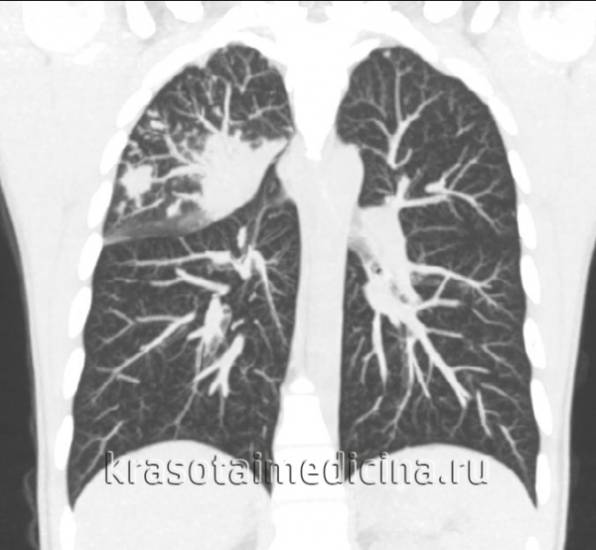

КТ органов грудной клетки. Множественные очаговые изменения верхней доле правого легкого (верифицированный туберкулез)